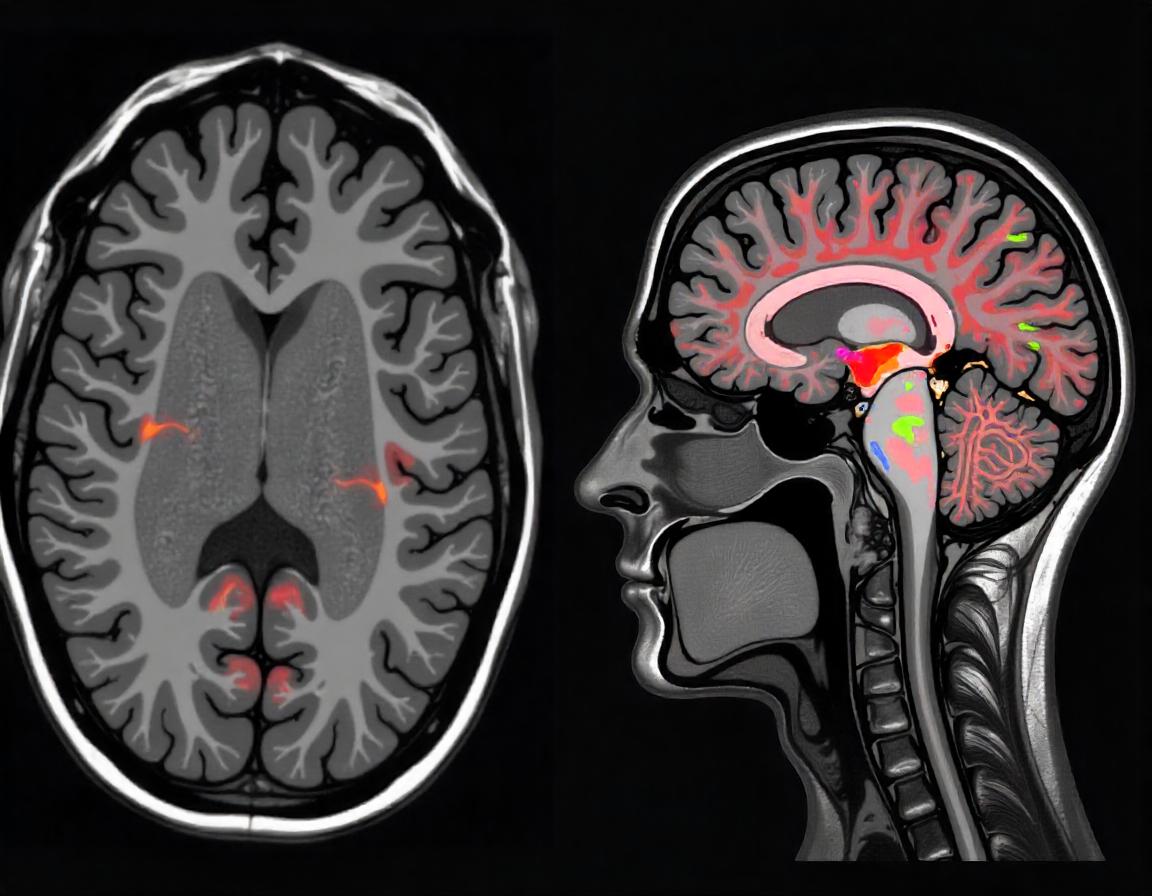

Нейровизуализация. Используется магнитно-резонансная томография (МРТ), чтобы оценить изменения в головном и спинном мозге, особенно на поздних стадиях. МРТ может показать атрофию (уменьшение объема) в определенных областях мозга, таких как мозжечок и спинной мозг, что характерно для атаксии Фридрейха, но не является патогномоничным. То есть, изменения будут, но диагноз верифицируется на основании генетического обследования.